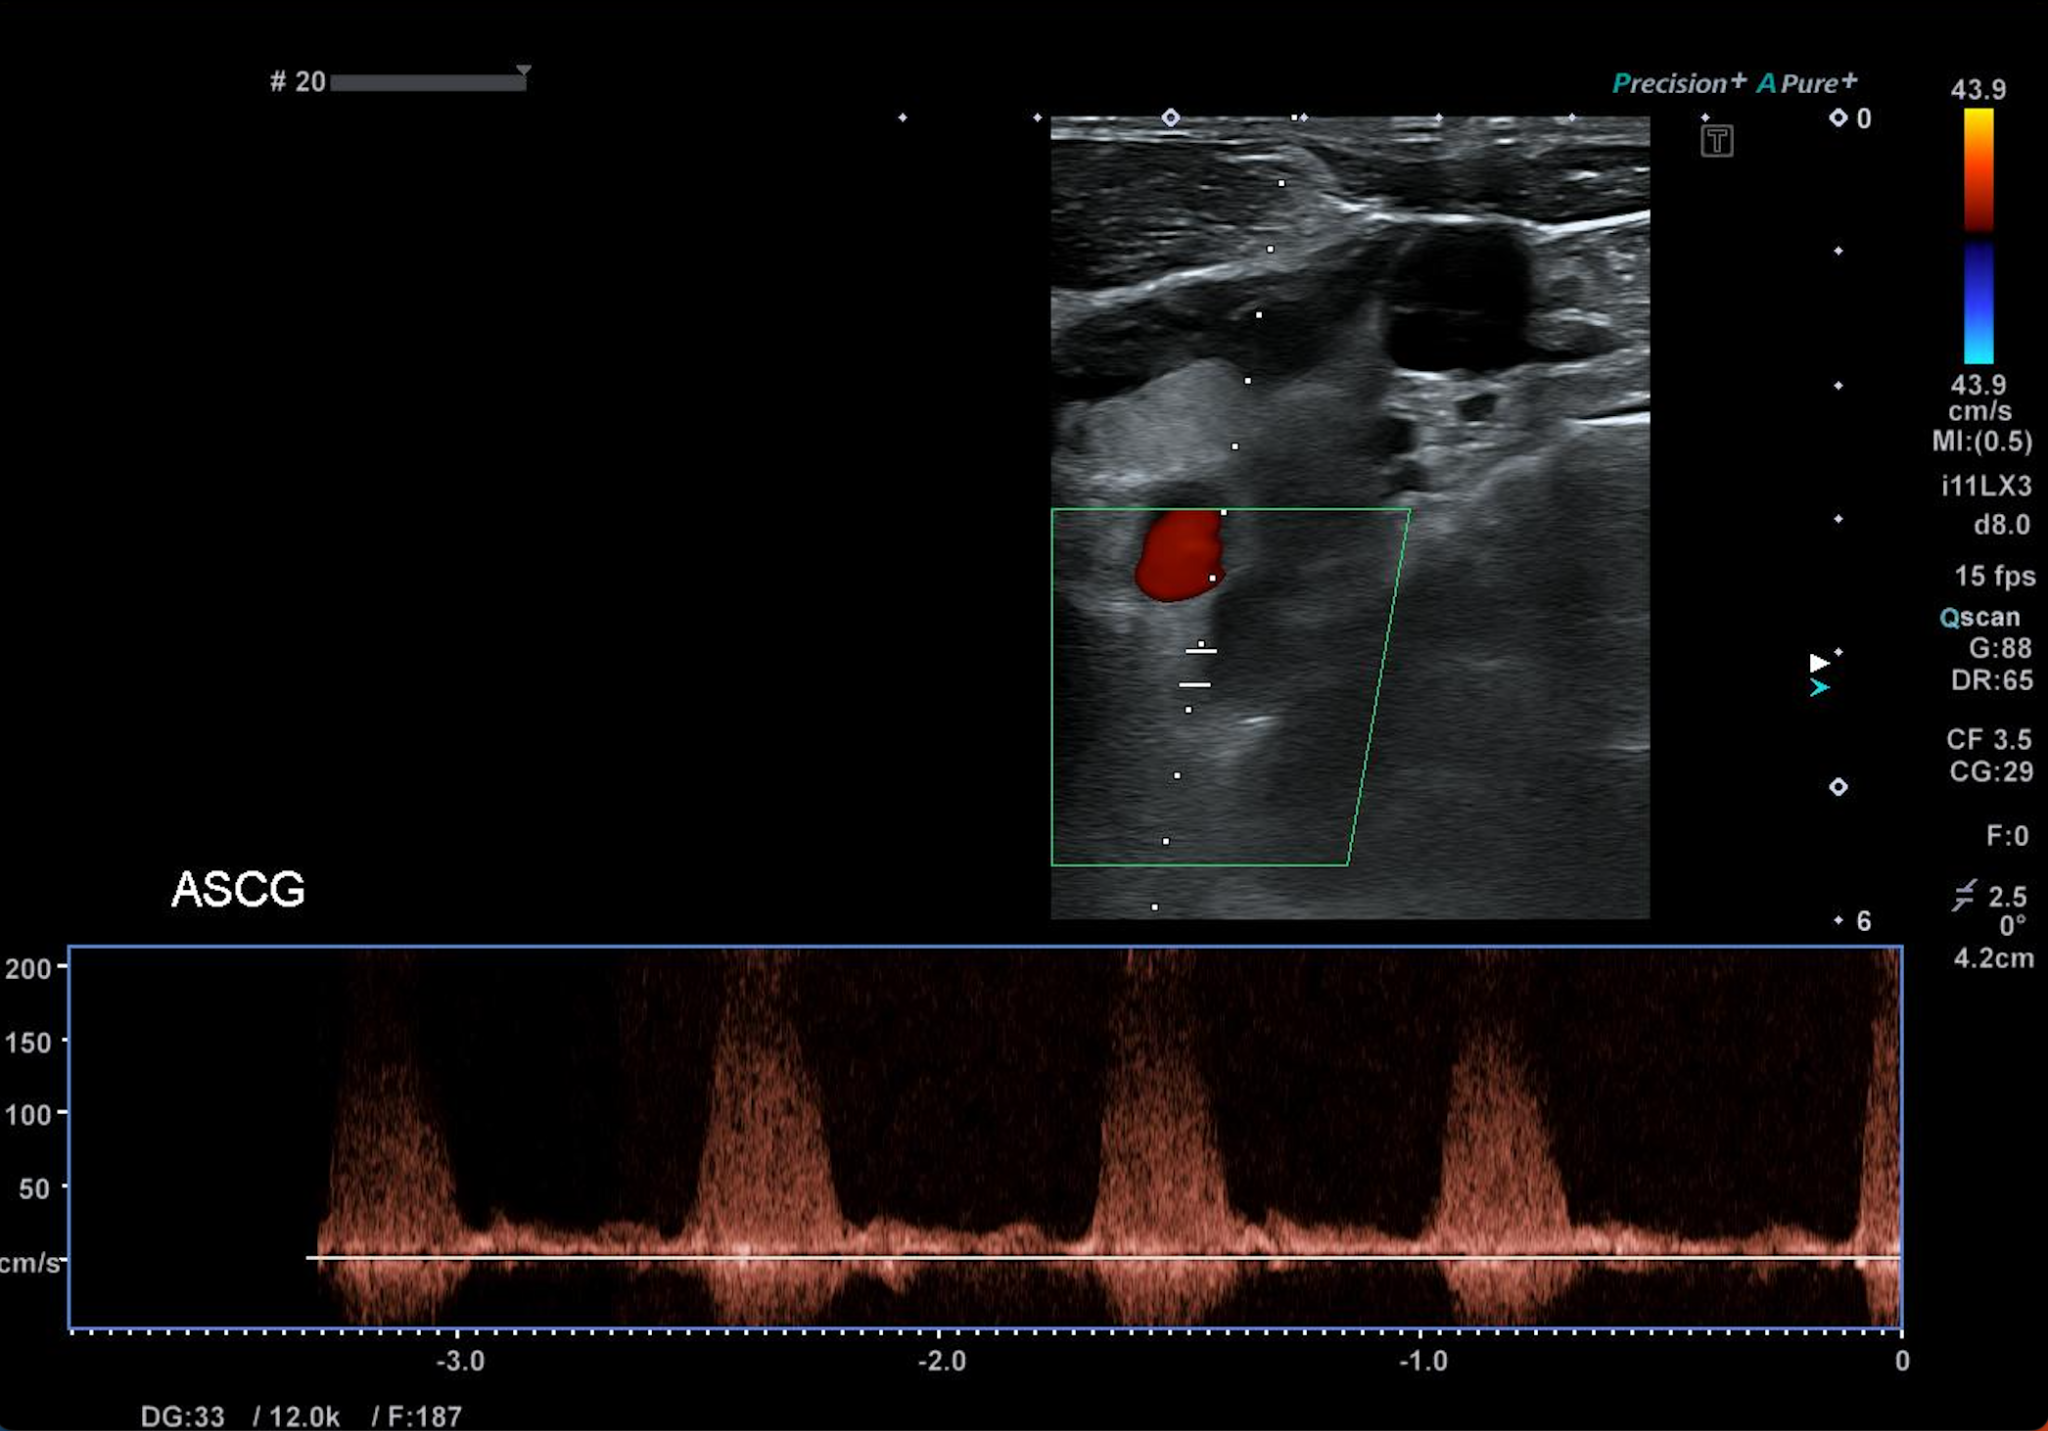

Nous retrouvons sans difficulté la sténose serrée de l’artère sous clavière gauche dans son segment prévertébral avec accélération des vitesses systoliques maximales et dispersion spectrale.

Il n’existe pas de démodulation au repos en aval de la sténose sur l’artère sous clavière.